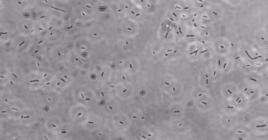

How Liquid-Handling Robots and Bacteriophage Cocktails Could Change Pharmacology Today